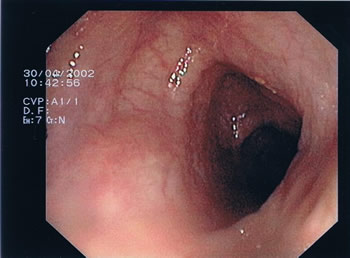

Endoskopische Bilder. Das Darmlumen innerhalb der einzelnen Darmabschnitte kann eher rundlich, leicht eingeengt oder dreieckförmig aussehen, entsprechend des anatomischen Aufbaus (s. Abb.1-4). Grundsätzlich gibt es verschiedene Arten von Polypen mit unterschiedlichen Konfigurationen und von verschiedener Größe. Kugelig(Abb.6) mit schmaler Verbindung zur Darmwand, hügelig mit breiter Basis, muschelförmig, die sich häufig an eine Querfalte anschmiegen, gestielte Polypen, die über einen Stiel mit der Darmwand verwachsen sind und sessile Polypen (Abb.5), die breitbasig auf der Darmwand aufsitzen. Der Übergang zum Dünndarm (Ileocaecal-Klappe) kann des Öfteren ein polypöses Aussehen vortäuschen (Abb.4).